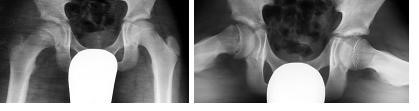

Przedstawione radiogramy stawów biodrowych w projekcji AP i osiowej (Lauensteina) 13 letniego pacjenta, skarżącego się na narastający ból stawu biodrowego i kolanowego przedstawiają:

Po zwiększonej aktywności na lekcji WF, 13-to letni pacjent zaczął utykać na kończynę dolną lewą i zgłasza dolegliwości bólowe stawu kolanowego lewego oraz okresowe dolegliwości lewego biodra. W badaniu klinicznym stwierdza się niewielkiego stopnia bólowe ograniczenie ruchów w stawie biodrowym z objawem Drehmana. Przed 2 dniami dziecko miało wykonano radiogram stawów biodrowych w projekcji AP (patrz poniżej), na którym pediatra rodzinny nie dopatrzył się zmian, zalecając odciążenie kończyny i leki przeciwbólowe. W celu ustalenia ostatecznego rozpoznania koniecznym jest wykonanie: